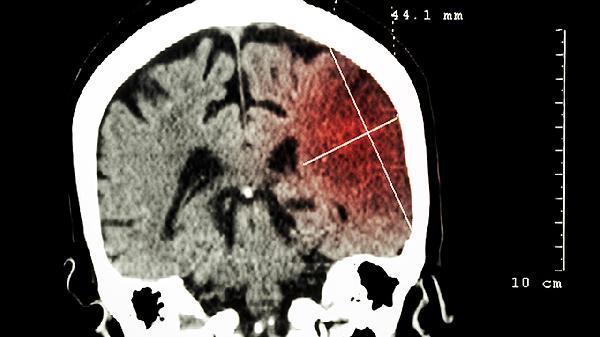

刺五加脑灵液具有清除自由基和抑制神经细胞凋亡的作用,对缺血性脑损伤有保护效果。可用于脑供血不足引起的头晕头痛,配合银杏叶提取物使用可能增强疗效,需警惕与抗凝药物的相互作用。